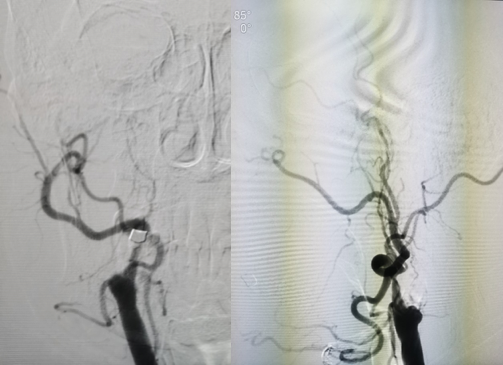

图2 造影见右侧颈内动脉起始处闭塞,闭塞处圆钝,可见自发再通后纤细扭曲血流,返流血较长,可达岩骨段-海绵窦段移行处

图3 通过前交通及后循环软膜支代偿,后交通未见明确开放,代偿情况可